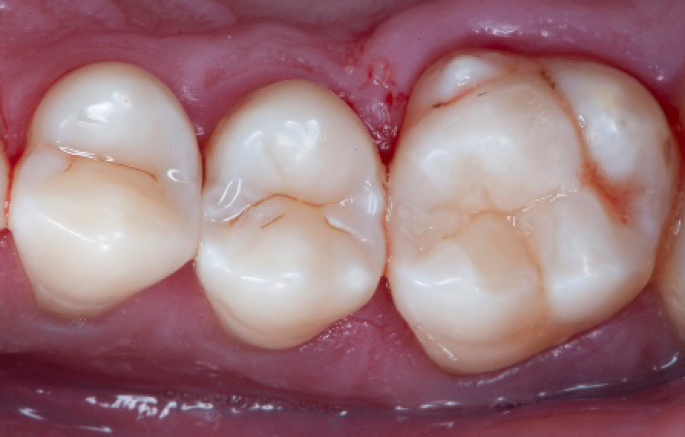

Step 12:

The situation after rubber dam removal.